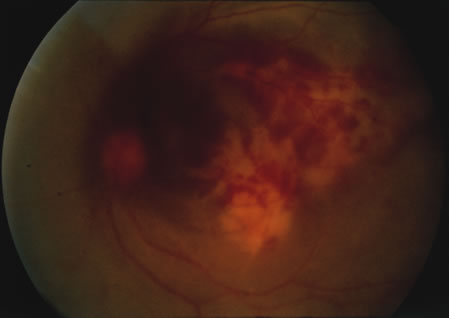

Retinal vascular lesions are the most common form of intraocular involvement in patients with SLE. The retinopathy most frequently consists of cotton-wool spots (Fig. 4) with or without intraretinal hemorrhages.208–210 The frequency of this finding varies depending on the patient population studied and the activity of the disease. One study209 found that only 3% of ambulatory outpatients had cotton-wool spots, while two separate studies180,210 found that 28% to 29% of hospitalized patients with active SLE had retinal vascular findings. This retinopathy occurs independently of hypertension and is thought to be related to the underlying microangiopathy of SLE. The histopathology of CNS lupus is that of a microangiopathic disease with small vessel vasoocclusion, a process presumed to be similar to that in the retina.211,212 Studies of autopsy material of patients with SLE have demonstrated immune reactants, primarily immunoglobulin and complement in the ocular vessel walls, and it has been suggested that these are the cause of the microangiopathy.213 Fluorescein angiographic studies have suggested that mild background retinopathy with microaneurysms and telangiectatic vessels may be relatively common.210

Fig. 4. Cotton-wool spots along the superotemporal arcade in a patient with active systemic lupus erythematosus.

The finding of retinal vascular changes in patients with SLE correlates with the activity of the disease.214 The relationship of cotton-wool spots alone to CNS lupus has been debated, but to date no relationship has been established. Most experts feel that the finding of cotton-wool spots does not indicate the presence of CNS lupus. A much less frequent, severe retinal vasoocclusive disease has been described and does appear to be associated with CNS lupus, in particular, diffuse CNS dysfunction, such as an organic brain syndrome.214–223 This more severe retinal vasoocclusive disease may present as a central retinal artery occlusion, central retinal vein occlusion, branch artery occlusion, or most frequently, a diffuse retinal vasoocclusive process (Fig. 5), sometimes called retinal vasculitis. Although this last process sometimes has been called retinal vasculitis, the exact pathogenesis may not be true vasculitis. Cases of severe retinal vasoocclusive disease in SLE in association with the lupus anticoagulant also have been reported, and the retinal disease in these cases is presumed to be secondary to this autoantibody (Fig. 6).190,191 The prognosis for vision with this diffuse retinal vascular disease is poor and retinal neovascularization commonly develops. Panretinal photocoagulation may be of value in the treatment of the neovascularization of severe lupus retinopathy. Approximately 50% of eyes affected with this severe vaso-occlusive disease become blind. Although visual loss is common in those patients with severe retinal disease, in the more common mild retinopathy visual loss is unusual.223